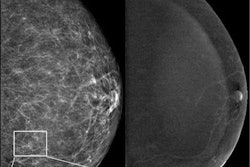

Can additional mammographic information beyond breast density -- computer-aided detection suspicion scores, for instance -- lead to improvements in predicting breast cancer risk? Investigators from Italy, Greece, and U.K. have addressed this question. Find out more in the Women's Imaging Community.